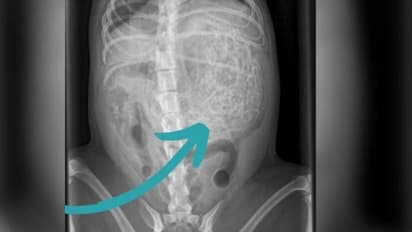

ഹാമിനെ പരിശോധിച്ച ന്യൂട്ടൺ ക്ലാർക്ക് വെറ്ററിനറി സർജറിയിലെ സംഘം പറഞ്ഞത് അവളുടെ വയറ്റിൽ അസാധാരണമായ എന്തോ ഒന്നുണ്ട് എന്നാണ്. അവസാനമാണ് ഈ അസാധാരണമായ സംഗതി 200 ഗ്രാം വരുന്ന ഹെയർബാൻഡുകളാണ് എന്ന് കണ്ടെത്തുന്നത്. ഏകദേശം 50 നും 60 നും ഇടയിൽ ഹെയർബാൻഡുകളാണ് ഹാമിന്റെ വയറ്റിൽ നിന്നും നീക്കം ചെയ്തത്.